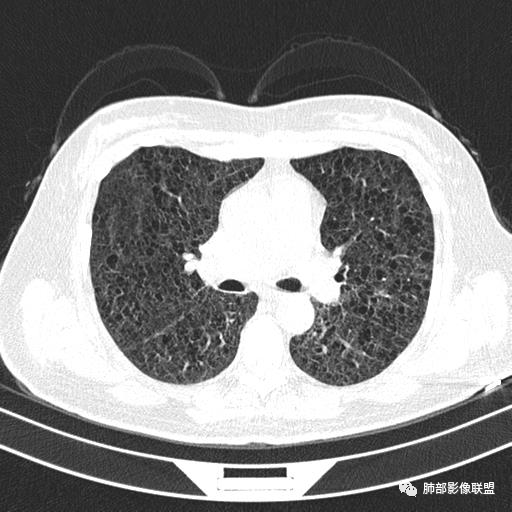

双肺弥漫囊腔,累及肋膈角,囊腔形态相对规则单一。

CT平扫示双肺弥漫分布大小不等囊状薄壁透光区,无内、中、外带分布差异,间质稍示增厚。拟LAM

中年女性育龄期妇女,咳嗽气喘,无吸烟史,有苯吸入史。影像:双肺弥漫均匀小囊腔,无明显分布优势,囊腔形态欠规则,壁薄,部分囊腔边缘血管征,伴双肺弥漫磨玻璃影,无结节,考虑lam,鉴别苯中毒肺损伤,囊腔多有分布优势,小叶中心分布为主,形态规整等

女,46,活动性气喘1年。苯吸入史半年。胸部CT:两肺弥漫囊腔,上至肺尖,下至肋膈角,形态类似小囊腔。考虑:LAM,鉴别LIP,BHD,PLCH等。

双肺弥漫大小不一薄壁含气囊腔,囊间肺组织正常,正常肺背景,肺尖肺底受累;青年女性,气喘,支持LAM

双肺多发大小相近的囊状影,分布趋势趋于一致,中年女性,考虑LAM。部分囊内见血管及分隔影,小叶中心性肺气肿代排

CT表现:双肺弥漫大小不等的薄壁囊腔,囊壁<2mm,外形规则,血管影多位于囊腔周围,囊腔之间肺组织正常,随着疾病进展到晚期,囊腔变大、增多,不可胜数,囊腔可融合成较大的囊,与肺气肿相似,形成间质性肺纤维化。部分病例可出现结节影。